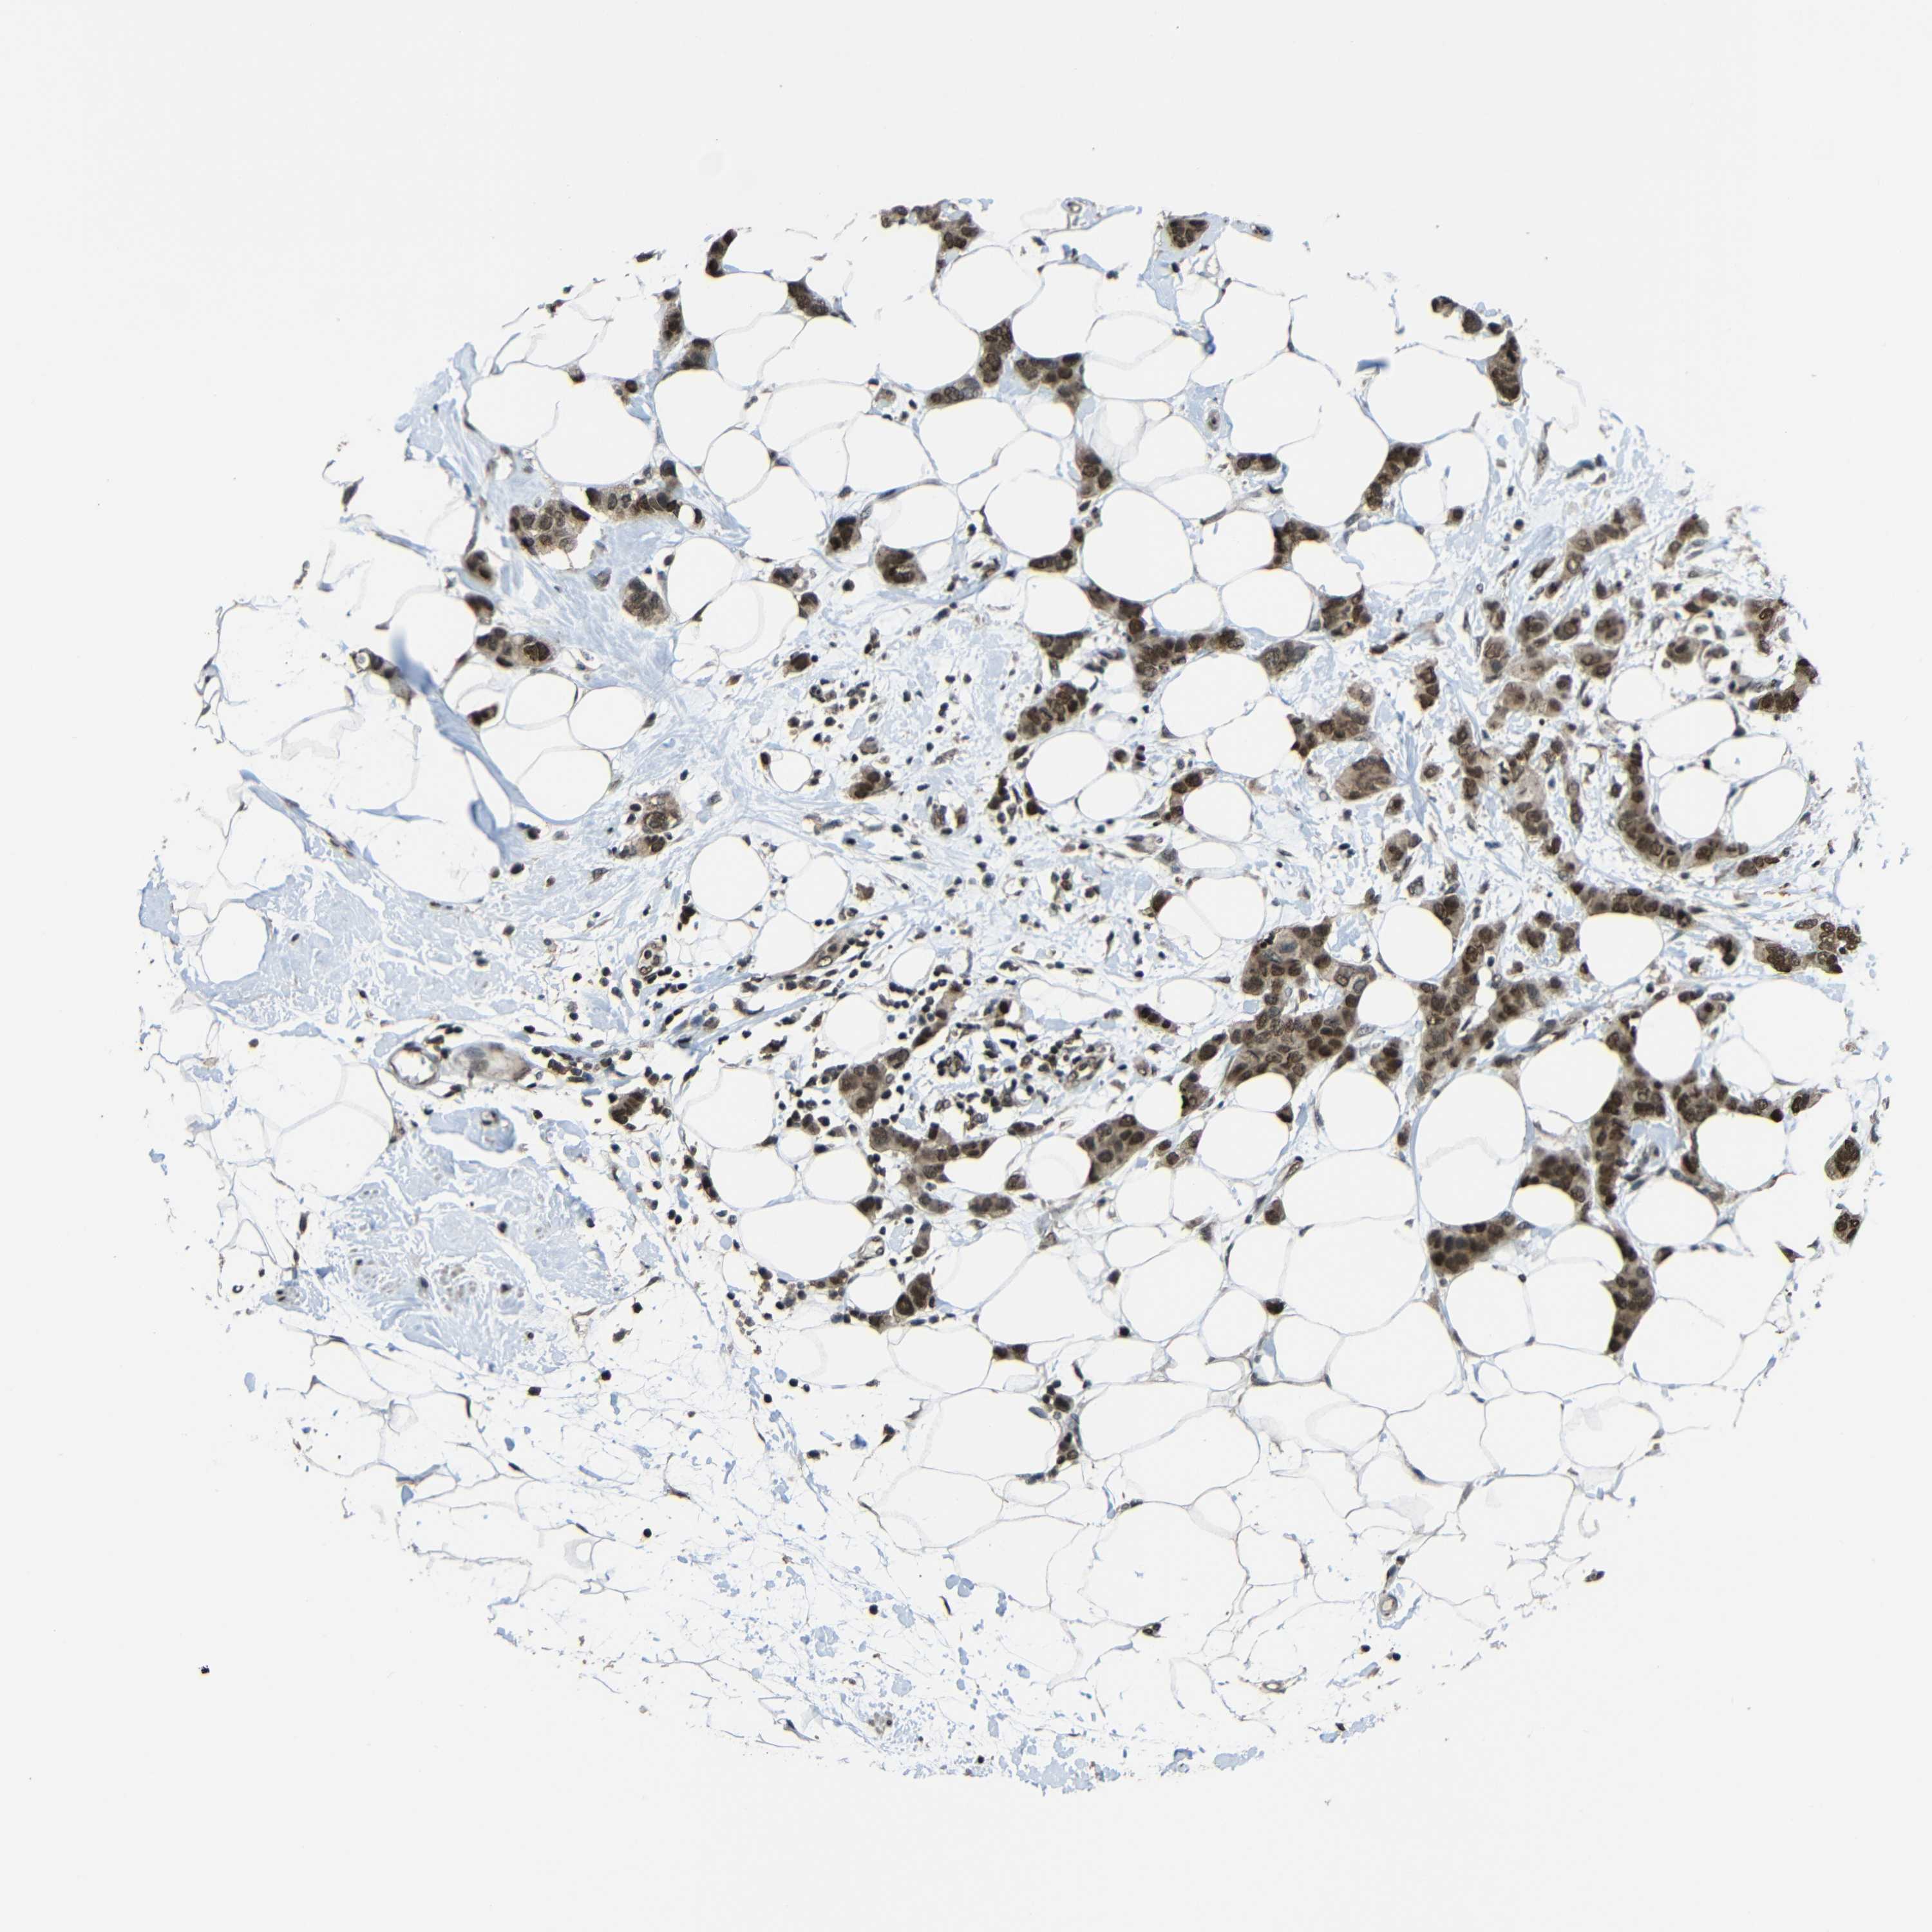

CANCER BREAST CANCER Show tissue menu

BRCA TCGA BRCA VALIDATION PROTEIN EXPRESSION